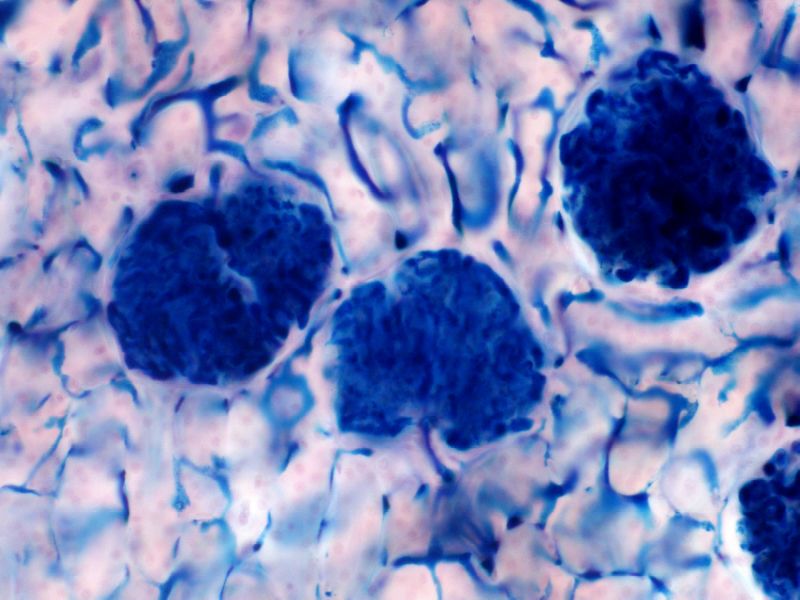

Podocytes

- Visceral layer of epithelium

- Protrude into capsular space

- Attached to basement membrane

- Long cytoplasmic extensions

- Primary processes

- Secondary processes

- Podocyte feet

- Tightly spaced

- Filtration slits 20 - 30 nm wide